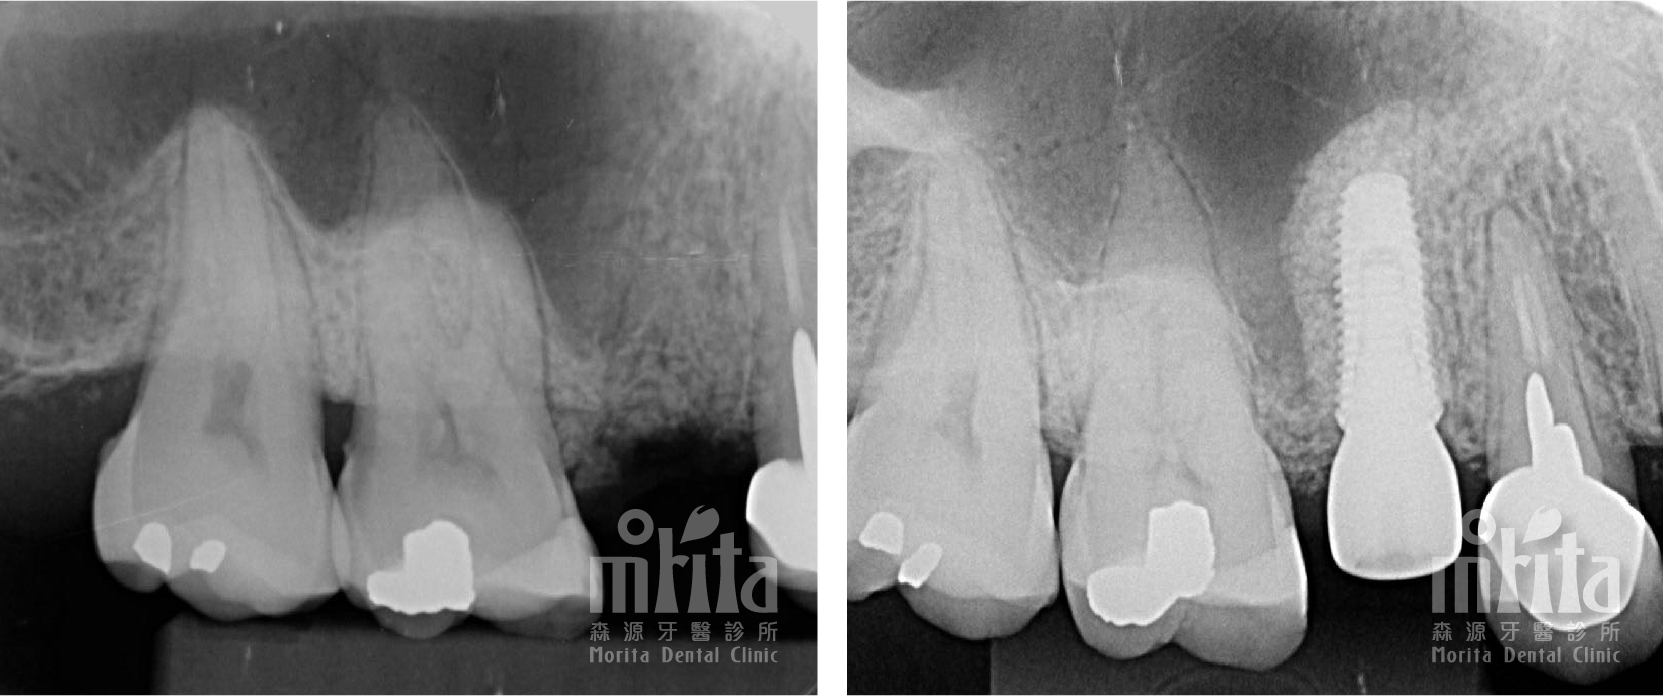

案例二:骨脊保存術 Ridge Preservation

案例二:骨脊保存術 X光片